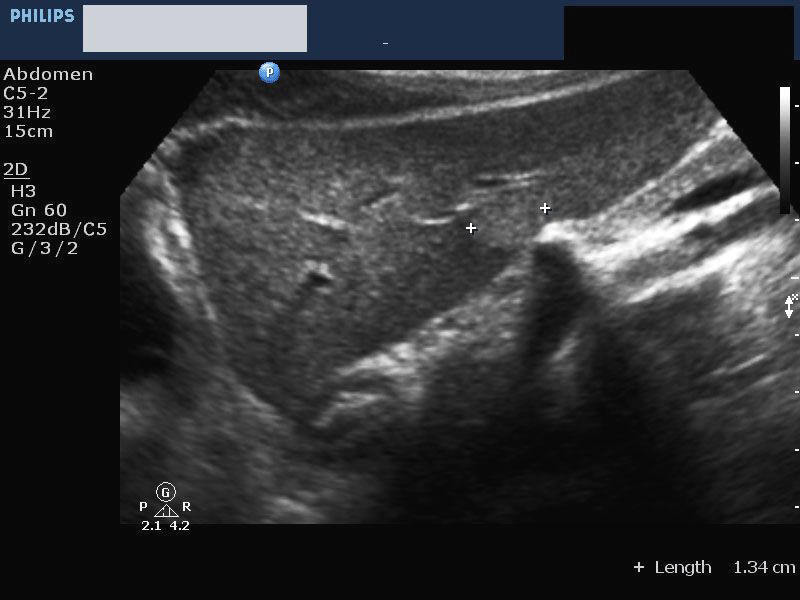

Elongated Left Lobe of Liver (the Beaver Tailed Liver)

Long left lobe of liver (normal variant).

In certain thin individuals (usually seen in thin women), the left lobe of liver appears elongated (see ultrasound images above), and overlies the spleen. In the above pictures, the spleen is seen to be hyperechoic compared to the left lobe (the so called "beaver tailed liver"). Ultrasound images courtesy of Dr. Ravi Kadasne, UAE. The machine used here is the Philips IU 22.